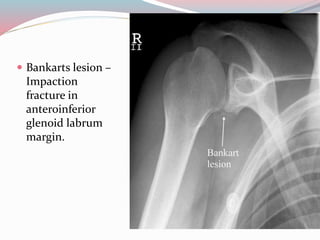

๏‚— Bankarts lesion โ€“

Impaction

fracture in

anteroinferior

glenoid labrum

margin.

๏‚— Bankarts lesionโ€“ Impaction fracture in anteroinferior glenoid labrum margin.